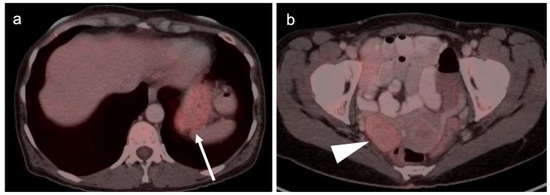

3.1. Prostate Cancer

3.2. Urothelial Carcinoma